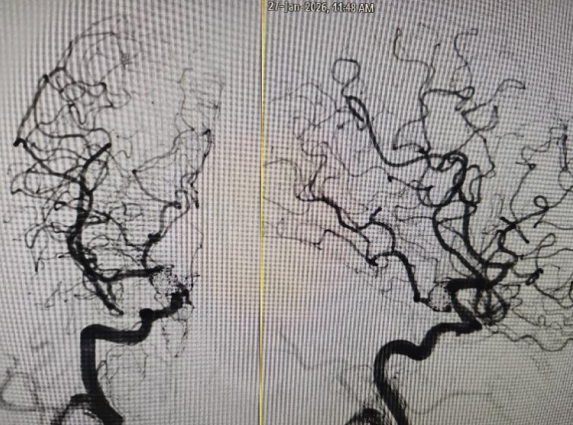

▲出血动脉瘤栓塞后不显影

经过全面评估,专家团队最终明确,尽管手术挑战大,但仍具备可控的救治希望,敲定采用介入微创颅内动脉瘤栓塞术,以最小创伤为老人拆除颅内“炸弹”。在充分向家属沟通病情、手术方案及潜在风险后,患者的手术如期进行。手术由钟书主任医师亲自主刀,陈杰飞副主任医师密切协助。在数字减影血管造影(DSA)引导下,医生通过微创导管将栓塞材料精准送达颅内病变位置,稳稳封堵动脉瘤,全程避开正常血管,最大限度减少对脑组织的损伤。历经约两小时的精细操作,患者破裂的动脉瘤被成功栓塞,颅内“定时炸弹”被安全拆除,手术取得圆满成功。